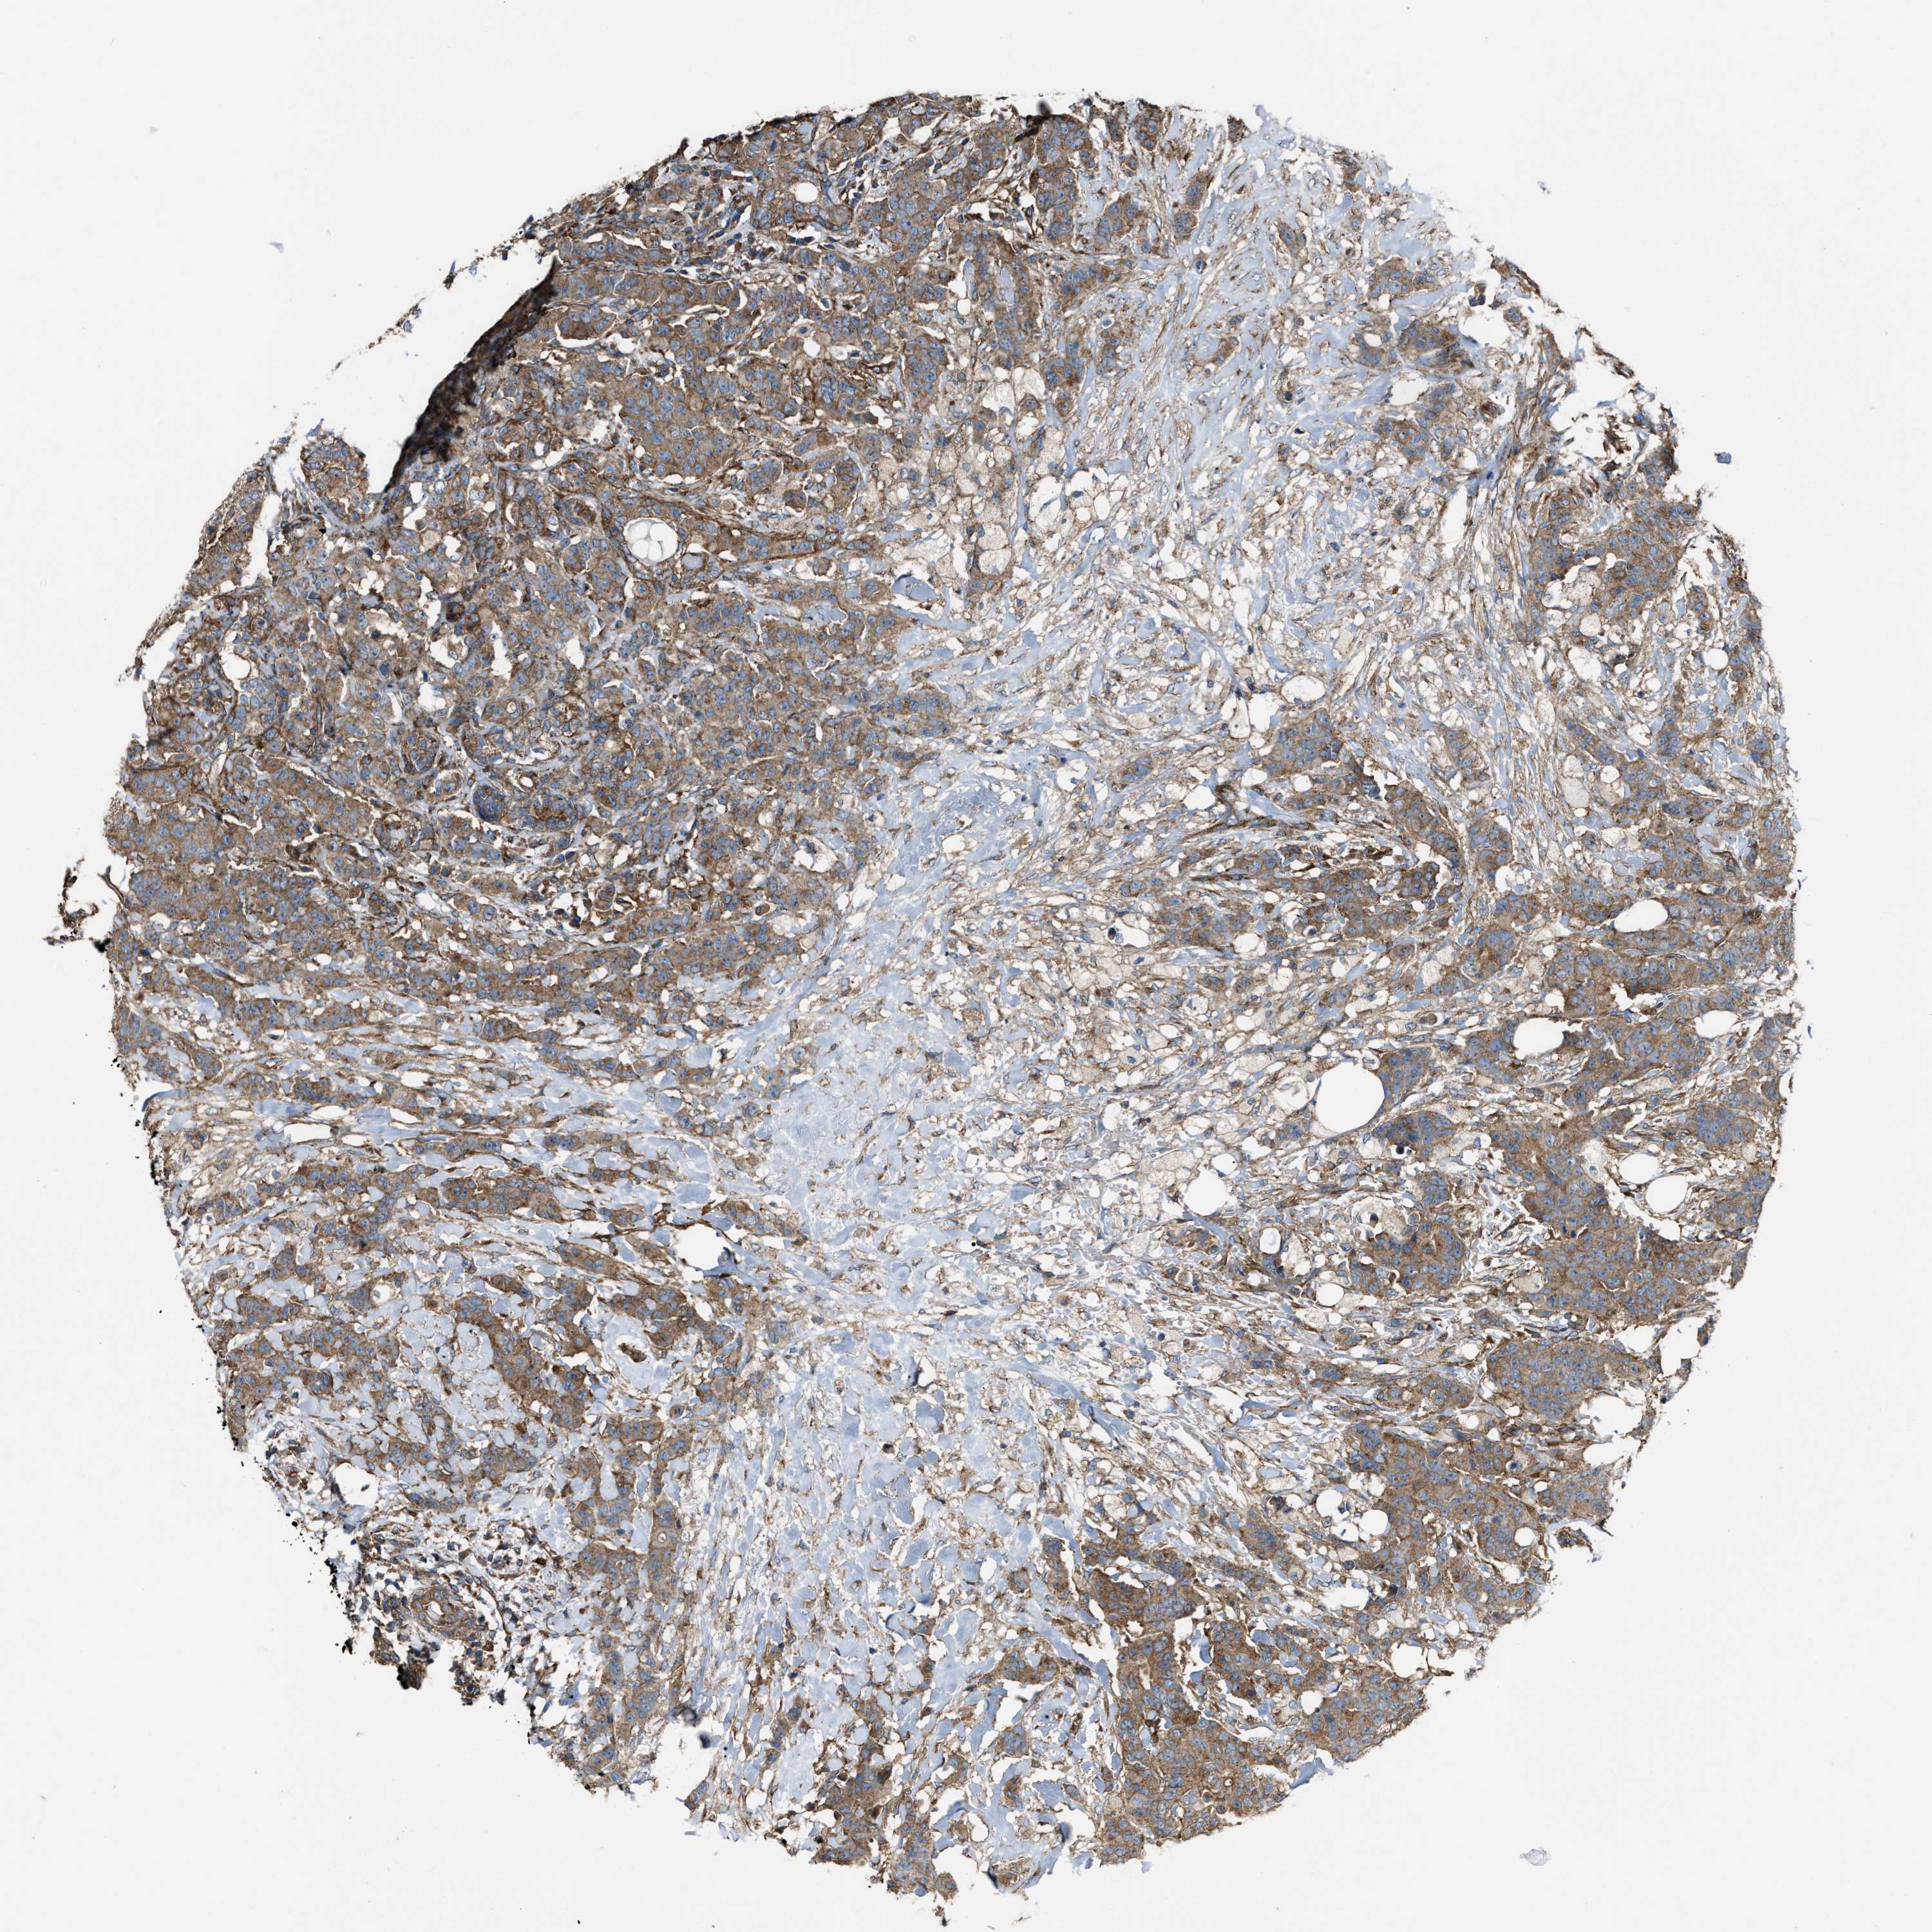

BRCA TCGA BRCA VALIDATION PROTEIN EXPRESSION